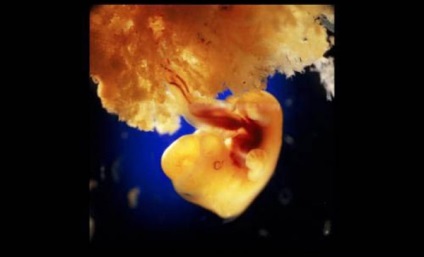

40 de zile. Celulele embrionare de exterior fuzionat cu suprafața pufoasă a uterului si forma placenta

10 săptămâni. Pleoapele sunt deja pe jumătate deschise. În termen de câteva zile, acestea vor forma complet.